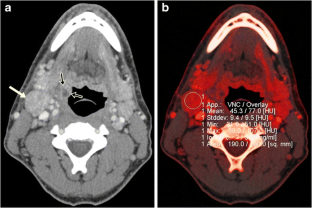

To evaluate whether dual-energy computed tomography (DECT)-derived iodine content and iodine overlay could differentiate between normal, inflammatory and metastatic squamous cell carcinoma (SCC) cervical lymph nodes.

This study was approved by the institutional review board. Sixteen patients with normal lymph nodes, 20 patients with enlarged nodes draining deep cervical inflammations and 23 patients with pathologically proved metastatic SCC nodes who underwent contrast enhanced DECT were retrospectively identified. Iodine content and overlay of 36 normal, 43 inflammatory and 52 metastatic lymph nodes were calculated using circular regions of interest and compared among the three groups. A receiver operating characteristic (ROC) curve was used to determine the sensitivity and specificity of iodine content and overlay for diagnosis of metastatic nodes.

Iodine content (mg/ml) was significantly lower for metastatic lymph nodes (2.34 ± 0.45) than for normal (2.86 ± 0.37) and inflammatory (3.53 ± 0.56) lymph nodes, P < 0.0001. Iodine overlay (HU) was also significantly lower for metastatic lymph nodes (47 ± 11.6) than normal (57.4 ± 8.2) and inflammatory nodes (69.3 ± 11.5), P < 0.0001. The areas under the ROC curve for iodine content and iodine overlay were 0.923 and 0.896.

DECT-derived iodine content and overlay differ significantly among normal, inflammatory and metastatic SCC cervical lymph nodes.